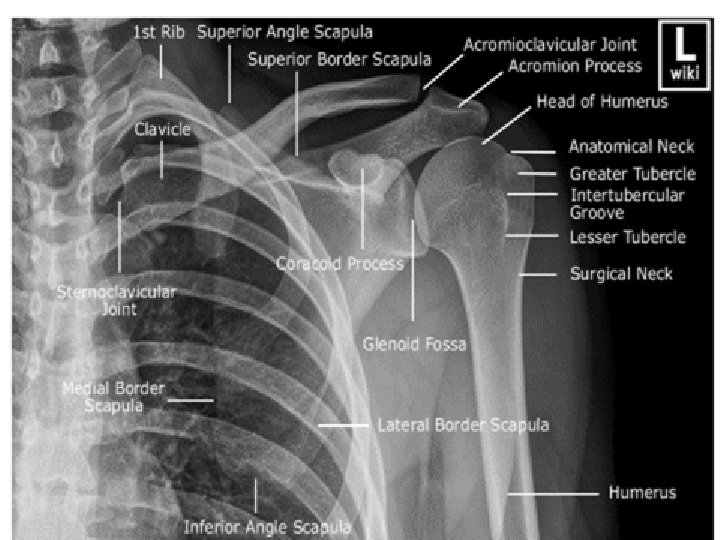

ARTICULATION 2 Articulation is between: The rounded head of the humerus and Glenoid cavity The shallow, pear -shaped glenoid cavity of the scapula.

3 The articular surfaces are covered by hyaline cartilage. The glenoid cavity is deepened by the presence of a fibrocartilaginous rim called the glenoid labrum.

FIBROUS CAPSULE 5 The fibrous capsule surrounds the joint and is attached: Medially to the margin of the glenoid cavity outside the labrum; Laterally to the anatomic neck of the humerus. The capsule is thin and lax, allowing a wide range of movement.

LIGAMENTS 3. The coracohumeral ligament strengthens the capsule from above and stretches from the root of the coracoid process to the greater tuberosity of the humerus. 6 Accessory ligaments: The coracoacromial ligament extends between the coracoid process and the acromion. Its function is to protect the superior aspect of the joint. 2. The transverse humeral ligament strengthens the capsule and bridges the gap between the two humeral tuberosities. 1. The glenohumeral ligaments are three weak bands of fibrous tissue that strengthen the front of the capsule.